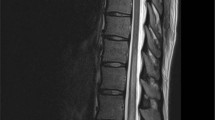

IN a recent symposium on experimental allergic encephalomyelitis there was considerable discussion on the size of encephalitogenic factors from brain and spinal cord1–4. We have fractionated extracts from bovine spinal cord by gel-filtration with phenol–acetic acid–water. This solvent system was introduced by Synge and colleagues5–7 for the fractionation of peptides on ‘Sephadex G-75’. It is a strongly dissociating solvent which prevents adsorption of peptides on ‘Sephadex’, and gel-filtration in this solvent can be used to estimate the molecular size of peptides as there is an approximately linear relationship between the relative elution volume and the log of molecular weight8,9. This communication describes a typical fractionation of basic polypeptides which were found to produce experimental allergic encephalomyelitis in guinea-pigs.